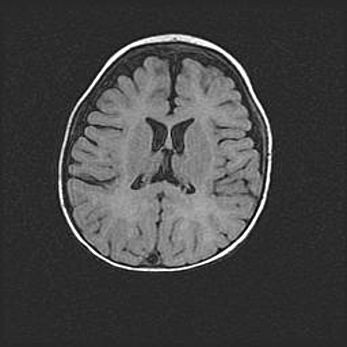

Открытая гидроцефалия.

Возраст: 9 месяцев 12 дней

Вес: 6800 г

Пол: мужской

Окружность головы: 41,5 см

Срок гестации: 28 недель

Гидроцефалия головного мозга у новорожденных имеет характерный признак: опережающий рост окружности головы приводит к визуально хорошо определяемой гидроцефальной форме сильно увеличенного в объёме черепа. Детские неврологи определяют следующие симптомы гидроцефалии у грудничков: выбухающий напряжённый родничок, частое запрокидывание головы, смещение глазных яблок к низу.